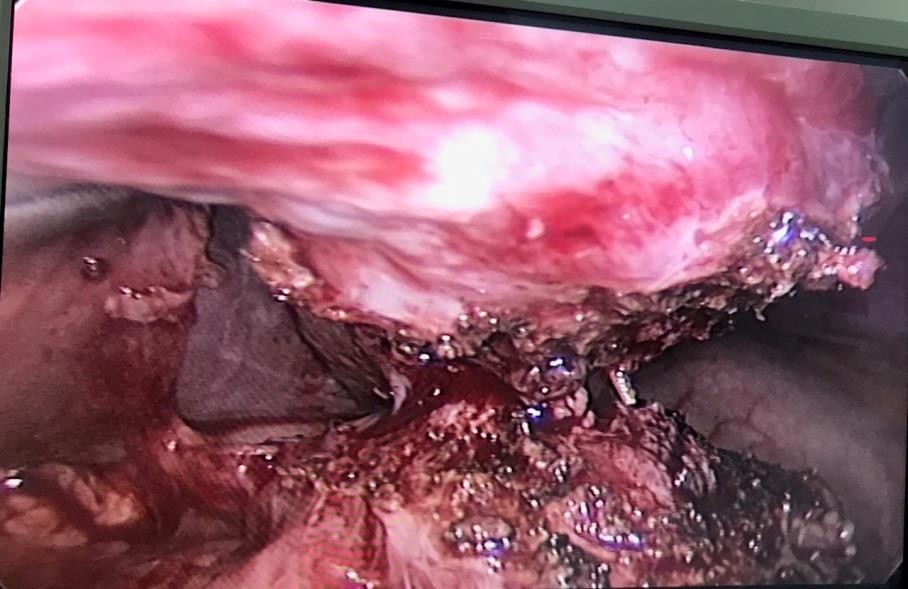

Một số hình ảnh ghi nhận trong và sau mổ:

Hình 4: Đầu tăm được phát hiện trong quá trình phẫu tích

Bệnh nhân được hội chẩn và được chỉ định nhập viện Khoa Ngoại Tiêu Hóa để được tiếp tục theo dõi và điều trị. Sau 3 ngày điều trị, tình trạng đau bụng bệnh nhân tăng nhiều hơn, thăm khám ấn vào vùng thượng vị cho thấy tình trạng đau tăng hơn nhiều, kèm cảm ứng phúc mạc (+) nên bệnh nhân đã được chỉ định mổ cấp cứu bằng phẫu thuật nội soi vào tối cùng ngày. Kết quả phẫu thuật cho thấy mặt dưới gan trái tạo thành khối viêm dính kích thước 30x20mm, phẫu thuật viên đã tiến hành phẫu tích và lấy ra 1 chiếc tăm tre dài 70mm xuyên thủng vào trong gan trái, kiểm tra dạ dày không phát hiện lổ thủng, các tạng khác không thấy tổn thương. Sau phẫu thuật 2 ngày, bệnh nhân ổn định, bụng mềm, vết mổ khô, ăn uống được, trung đại tiện bình thường. Dự kiến sẽ cho ra viện trong vài ngày tới.